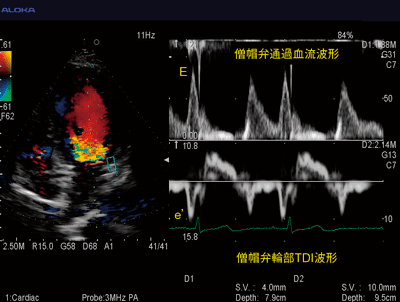

心房細動は,臨床現場で最も一般的に見られる不整脈で,心不全のリスクを増大させる因子であることから,左室機能を評価することは臨床的に重要であると言われている。一方で,従来,心房細動患者においては心室の興奮が不規則となるため,安定したR-R間隔が得られず,正確な評価が困難であった。そこで,Dual Dopplerを用いることにより,同一時相における僧帽弁口血流速波形の拡張早期波(E波)と,僧帽弁輪運動速波形の拡張早期波(e’波)の計測が可能となり,より正確な拡張能評価が可能となった(図4)。

図4 Dual DopplerによるE/e’の評価

(画像ご提供:徳島大学病院循環器内科超音波センター・山田博胤先生)